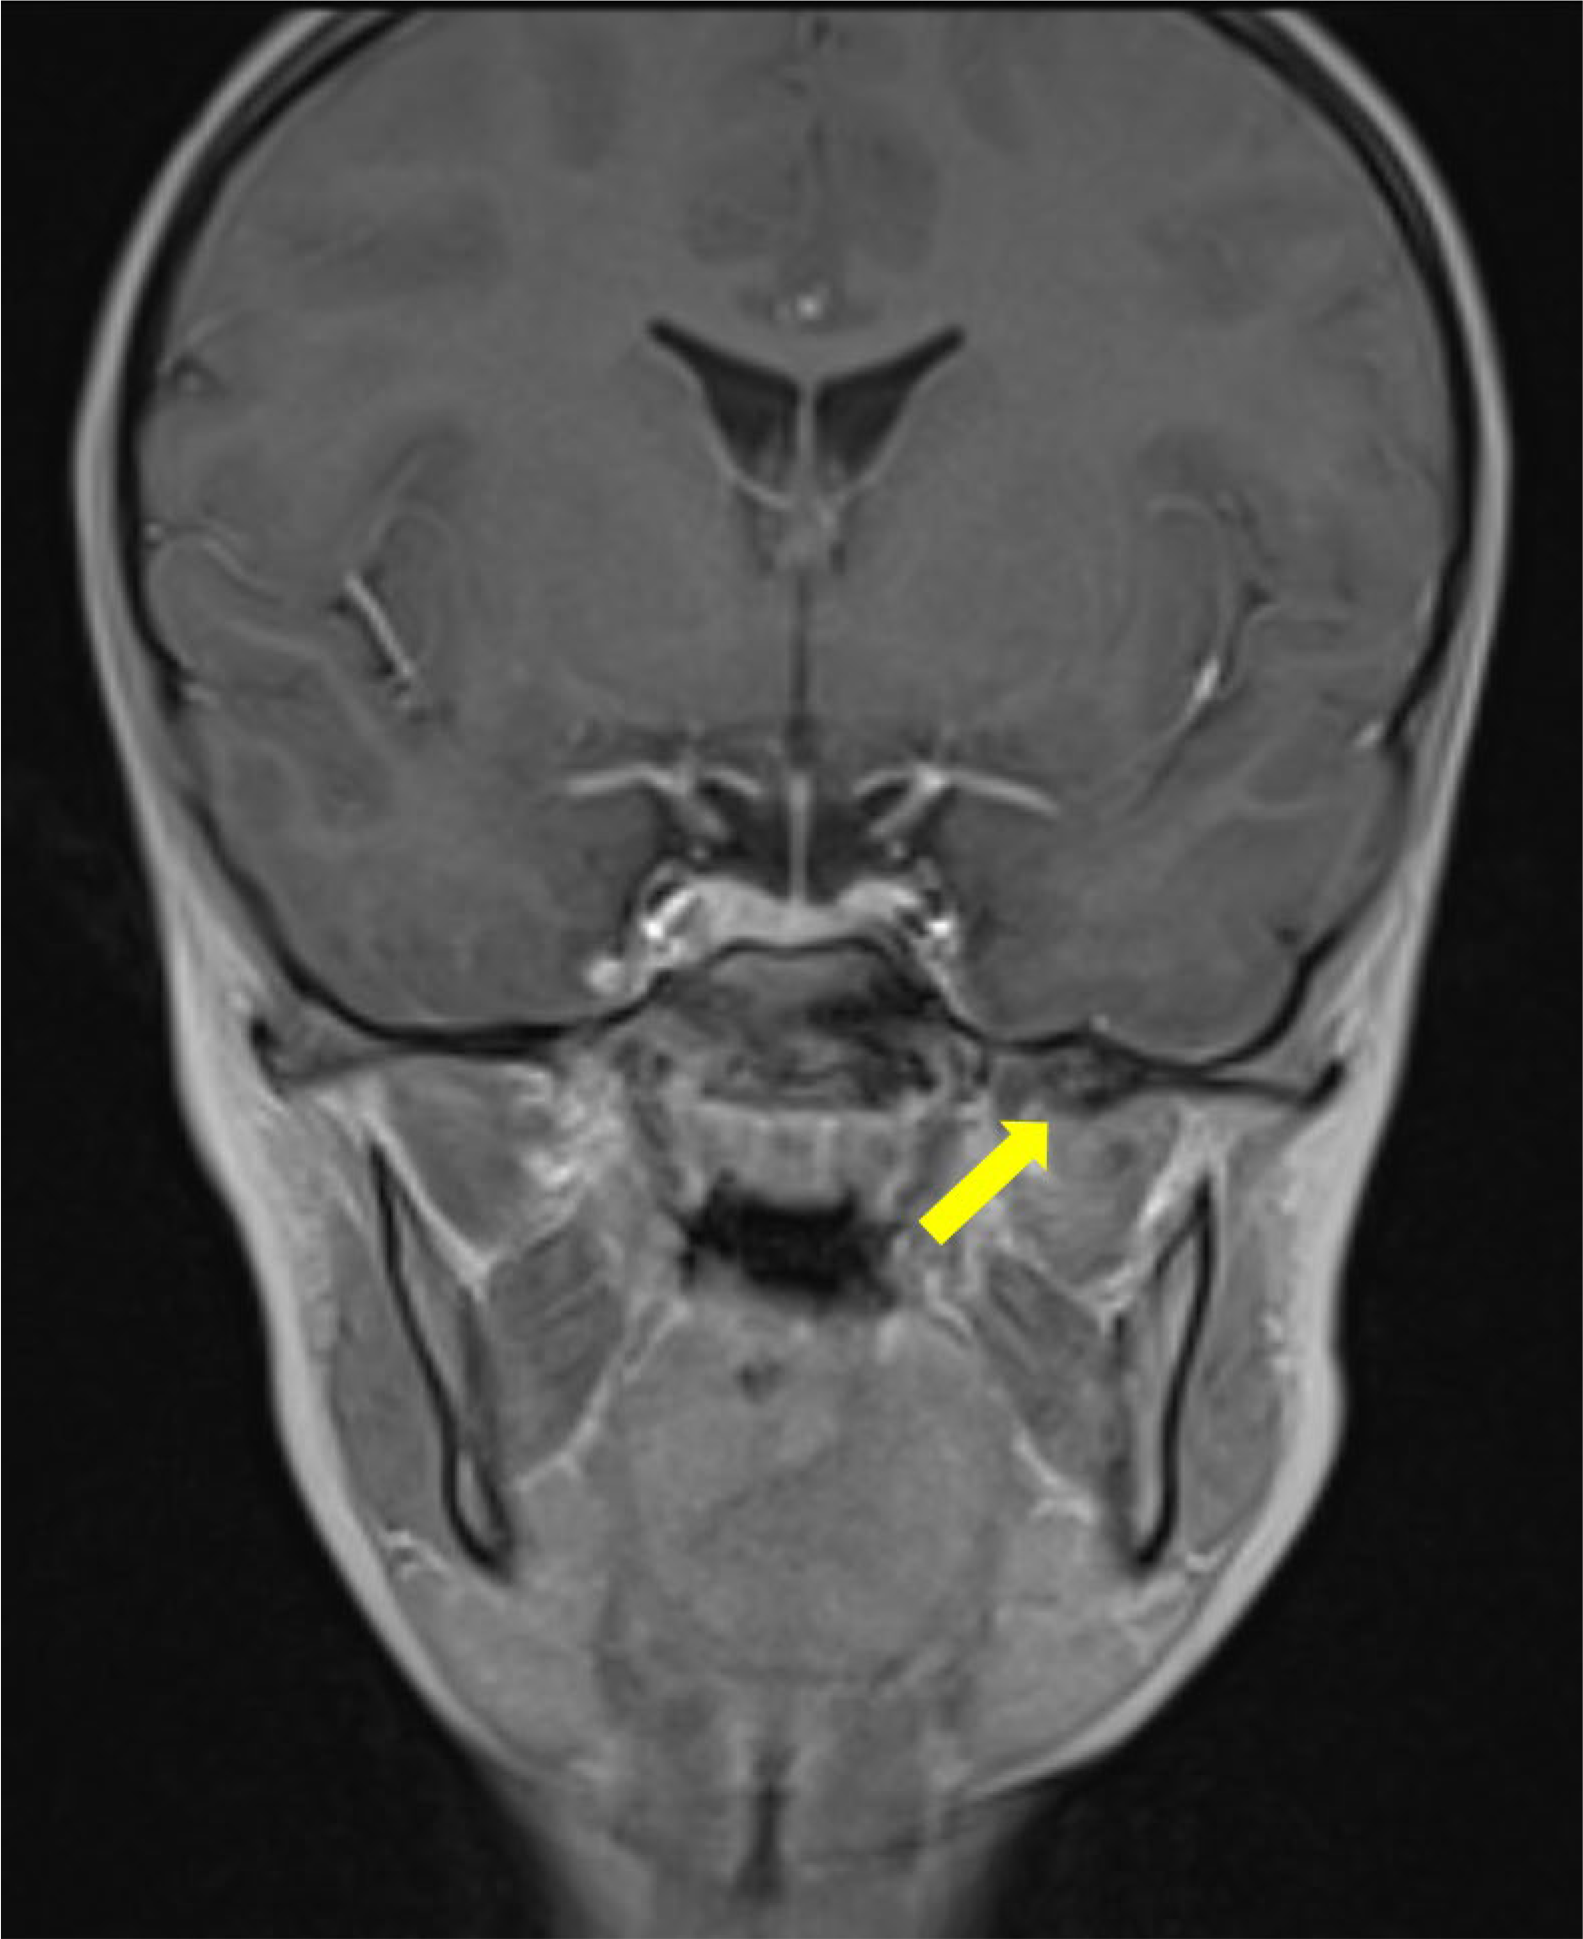

Figure 2

Contrast enhanced coronal T1 Dixon MRI scan showing the bony signal of the bony structure of the sphenoid spine (arrow) with no enhancement on the fat‑suppressed reconstructions (not shown).